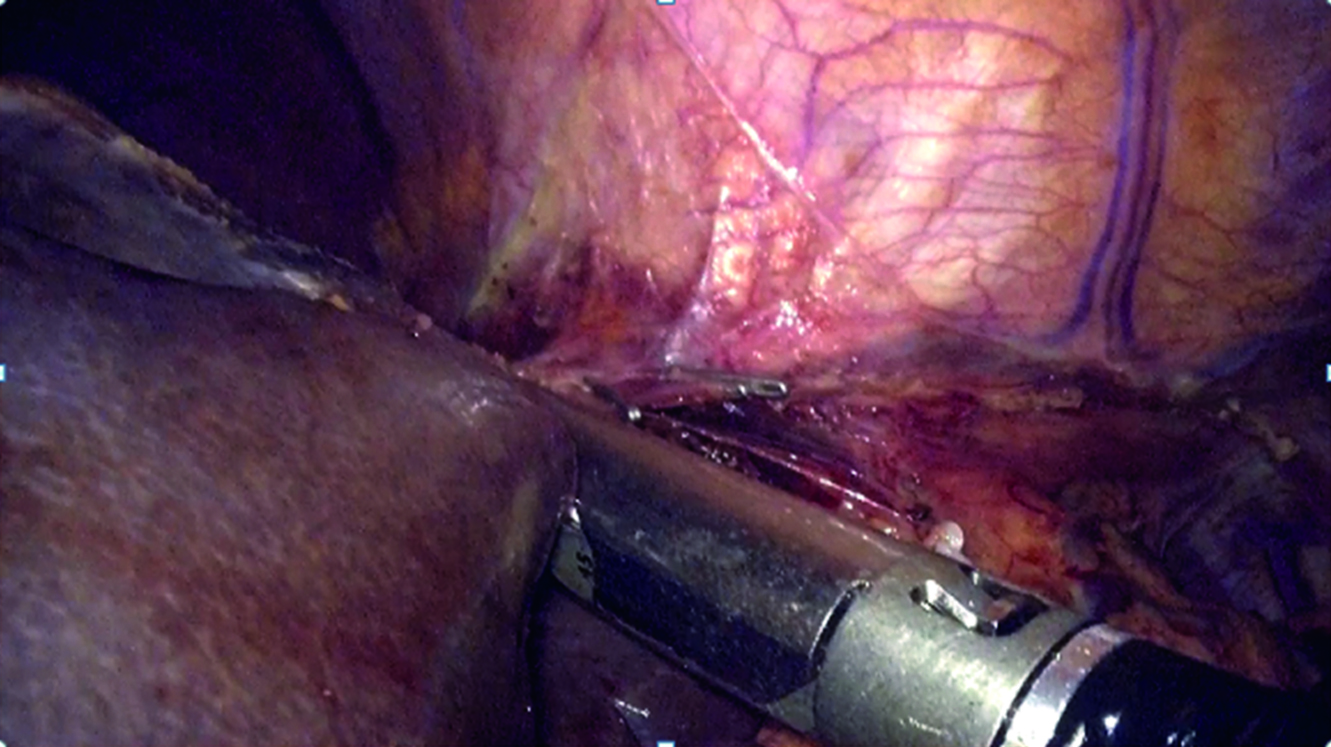

Left-side hemohepatectomy was performed with resection of the SV, SVIII. The left and the middle hepatic veins were visualized which were crossed and stapled with the Echelon Stapler (Fig. 6).

Figure 6. Crossing of the left and middle hepatic veins.

Рисунок 6. Пересечение левой и средней печеночных вен.